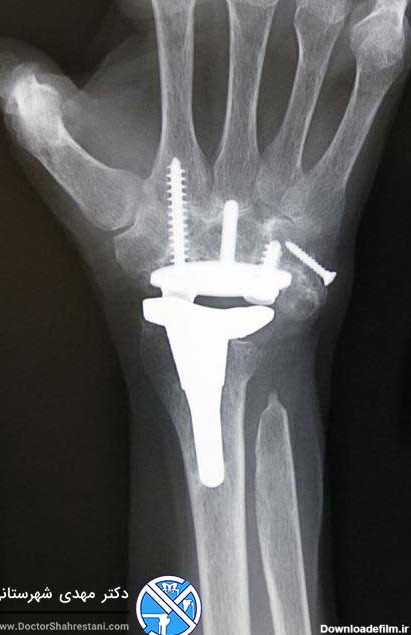

آرتریت شامل التهاب یک یا چند مفصل است. درد و سفتی جزء علائم متداول آرتریت محسوب می شوند، و در زمان بروز این علائم در مچ دست، فعالیت های ساده روزمره می تواند با مشکل مواجه شود. آرتریت انواع مختلفی دارد و بیش تر این موارد می توانند مچ دست را درگیر کنند. هرچند شدت […]